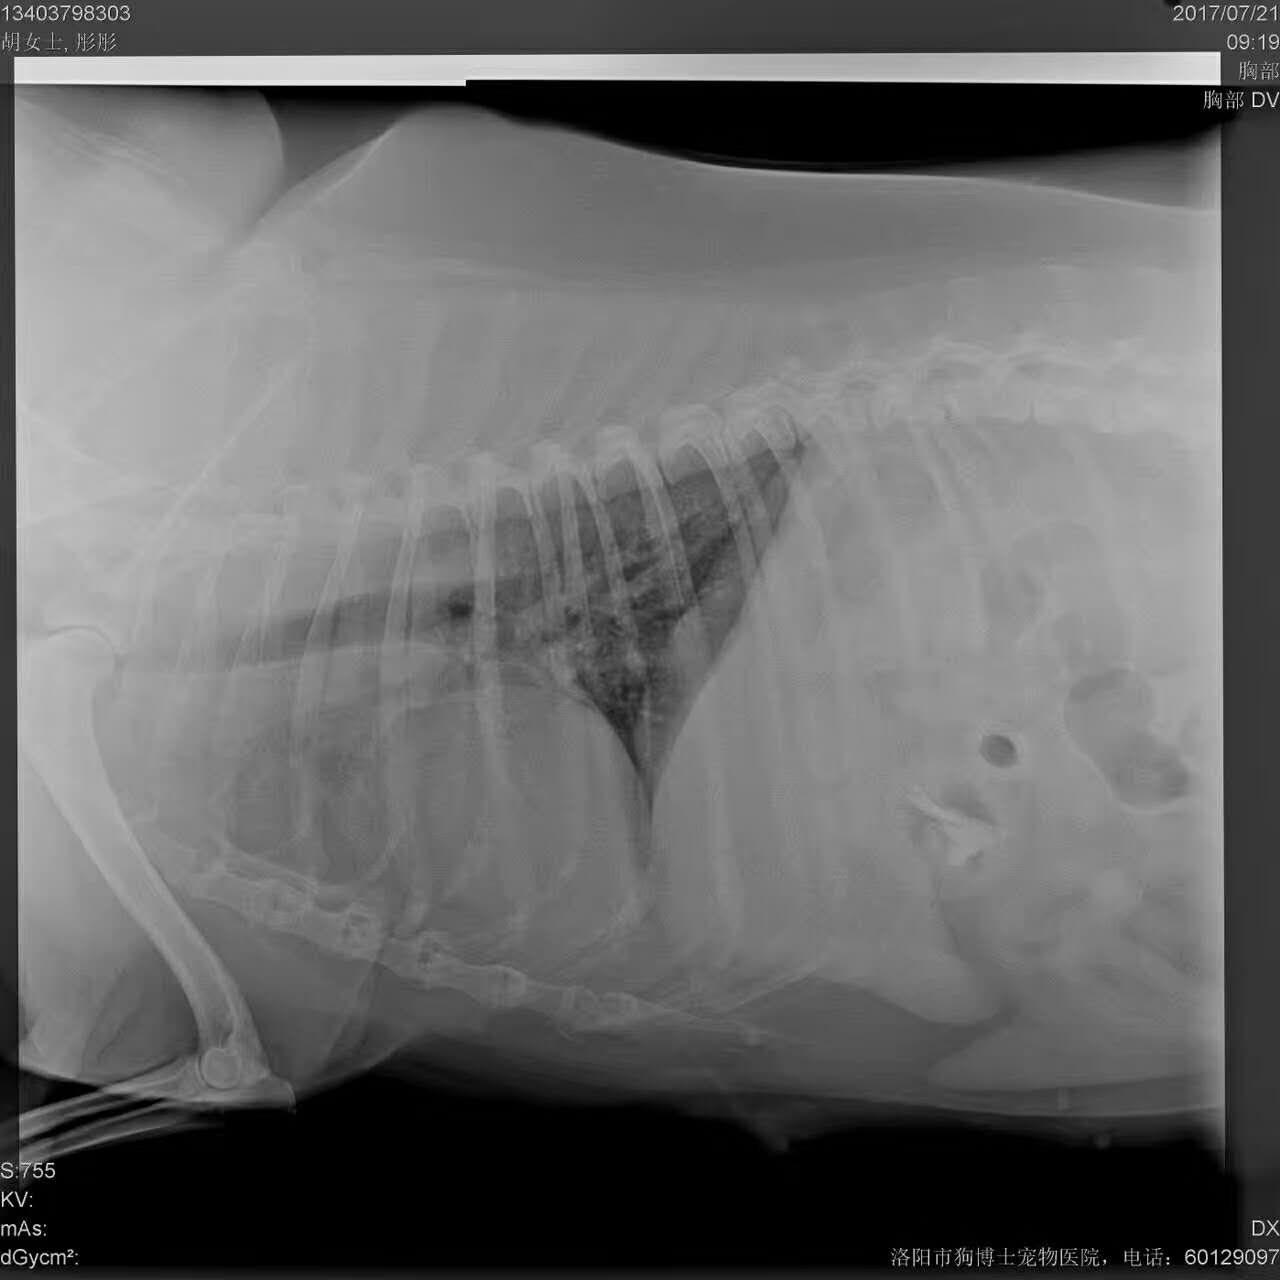

薩摩耶:同同,11歲,未絕育,約一年前發(fā)現(xiàn)腹部乳頭有瘤狀物生長(zhǎng),今年不斷變大,來(lái)本院就診為乳腺腫瘤?卵泡囊腫(左側(cè)11cm*6cm,右側(cè)數(shù)個(gè)直徑約0.5cm卵泡),實(shí)施腫瘤摘除?絕育手術(shù),一起順利,狗狗已經(jīng)蘇醒。溫馨提醒:不以繁殖為目的養(yǎng)寵,請(qǐng)盡早為她做絕育,這樣她們可以多陪你幾年。